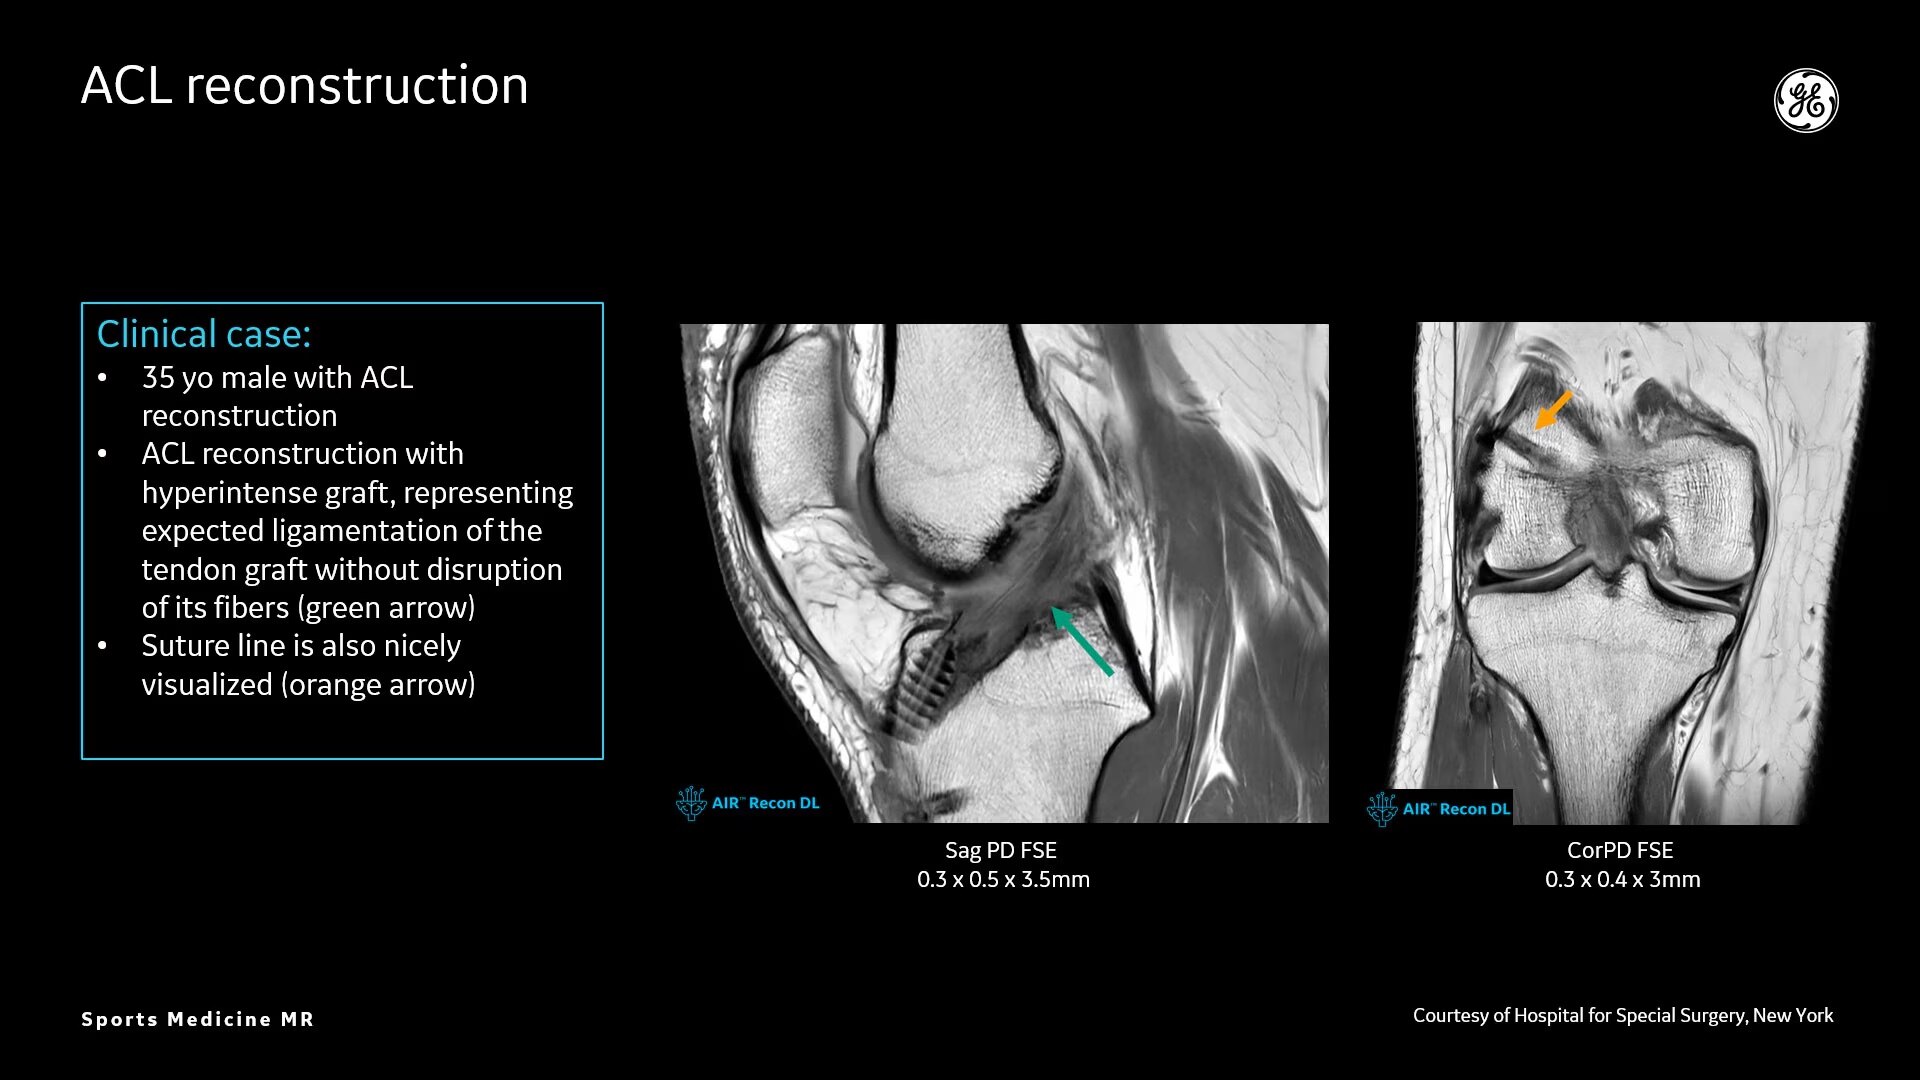

Deep-Learning MR Image Reconstruction Algorithm

High spatial resolution imaging

AIR™ Recon DL provides high-resolution images with increased SNR at markedly reduced scan times. This technology optimizes the depiction of even small injuries, such as meniscal, labral and ligament tears. The reduction in scan times increases flexibility for individually tailored MR protocols with an additional oZTEo sequence for detailed fracture assessment.